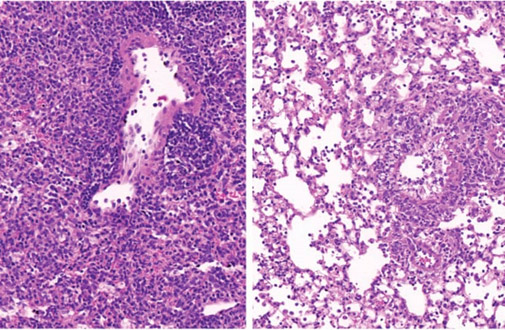

El tejido pulmonar de un ratón diabético (derecha) contiene menos células inmunitarias (pequeños puntos morados) que el de un animal no diabético (izquierda).(crédito de la foto: INSTITUTO DE CIENCIA WEIZMANN)

Se sabe desde hace décadas que los diabéticos y prediabéticos con niveles elevados de azúcar en sangre (hiperglucemia) tienen un riesgo sustancialmente mayor de desarrollar enfermedades pulmonares graves si se infectan con virus como la gripe, así como con bacterias y hongos.

Este misterioso fenómeno se volvió aún más apremiante cuando la pandemia de COVID-19 comenzó a principios de 2020. Quedó claro que los diabéticos estaban en una situación mucho más grave. mayor riesgo de contraer una enfermedad pulmonar grave, incluso mortal, después de desarrollar una forma grave del virus. Sin embargo, nadie entendió por qué. De hecho, alrededor del 35 % de las víctimas del coronavirus que murieron durante la pandemia tenían diabetes.

Ahora, una investigación realizada en el Instituto Weizmann de Ciencias en Rehovot ha revelado cómo, en los diabéticos, los niveles elevados de azúcar en sangre alteran la función de subconjuntos de células clave en los pulmones que regulan la respuesta inmune. También identifica una estrategia potencial para revertir esta susceptibilidad y salvar vidas.